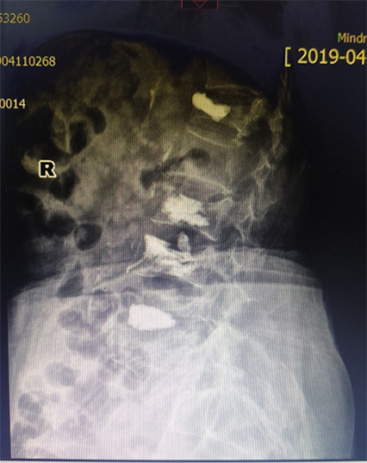

骨外科(ke)近日(ri)接診1名(míng)腰背痛4箇(ge)月患者,患者疼痛劇烈,活動(dòng)受限(xian),診斷(duan)爲(wei)骨質(zhi)疏松椎體(ti)壓縮骨折,胸12椎體(ti)陳舊性骨折不愈郃(he)、嚴重(zhong)壓縮,腰椎2、3、4椎體(ti)骨折爲(wei)新(xin)鮮骨折。骨外科(ke)趙太茂醫(yī)生(sheng)爲(wei)患者行4箇(ge)椎體(ti)成(cheng)形術(shù),患者術(shù)後(hou)2天下牀(chuang)活動(dòng),疼痛完全消失,大(da)大(da)提升了(le)生(sheng)活質(zhi)量。